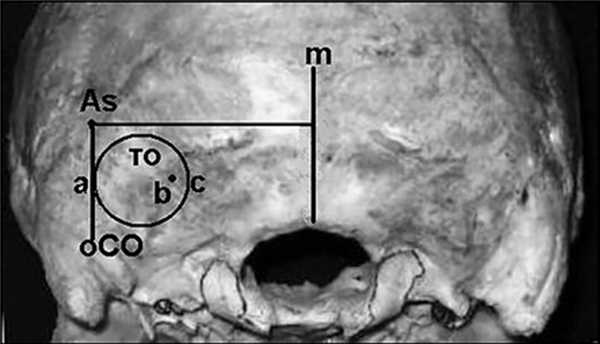

Расположение точки входа оси бурения «А» на задней грани пирамиды височной кости фиксировали, измеряя расстояние от этой точки до наружного края трепанационного окна. Наружную границу трепанационного окна «а» всегда располагали на линии между точками «АСТЕРИОН» и задним основанием сосцевидного отростка. Точку выхода оси бурения «b» на поверхность затылочной кости определяли в системе координат относительно срединной линии «m» в сагиттальной плоскости и линии проведенной от точки «АСТЕРИОН» в аксиальной плоскости, медиальную границу трепанационного окна «с» определяли от точки выхода оси бурения, прибавив расстояние рабочей части бора (рис. 4).

Рис. 4. Схема определения латеральной (а) и медиальной (с) границ трепанационного окна (то) и точки оси бурения (b) на поверхности затылочной кости. — средняя линия, As — точка «АСТЕРИОН», оСО — точка заднего основания сосцевидного отростка.